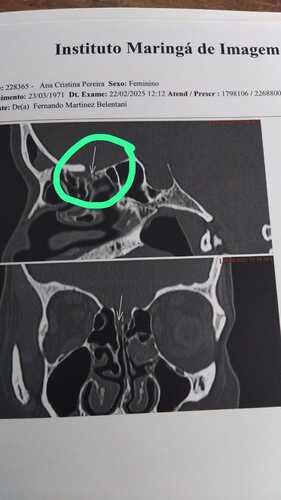

Sou a Ana Cristina, e preciso de cirurgia com urgência, pois sofri um trauma na cabeça que ocasionou a quebra de um osso do meu crânio, o que fez romper uma membrana do crânio. Essa fissura faz com que o líquido de uma das membranas de proteção cerebral extravase, deixando a pressão e proteção do cérebro alterada, além de abrir caminho para vírus e bactérias. Qualquer valor é bem-vindo e ficarei muito agradecida.